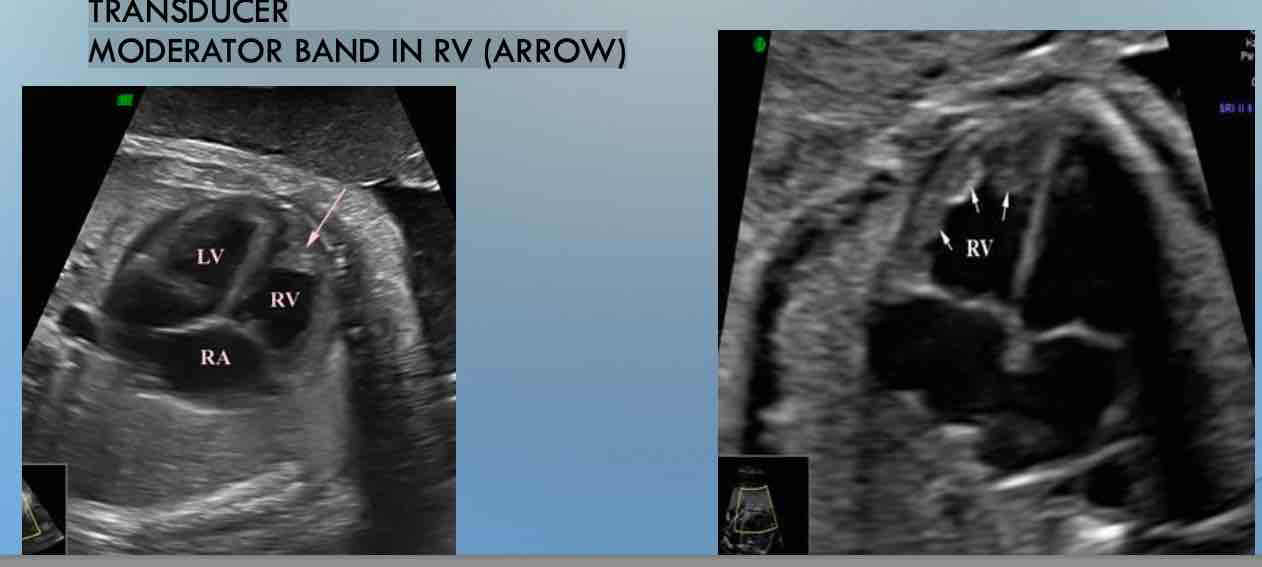

APICAL FOUR CHAMBER VIEW OF THE HEART

TRANSVERSE VIEW OF FETAL CHEST

APEX OF THE HEART POINTING DIRECTLY TOWARD OR AWAY FROM

TRANSDUCER

INTERVENTRICULAR SEPTA AND INTERATRIAL SEPTA ARE PARALLEL TO THE

MODERATOR BAND IN RV (ARROW)

Moderator band

location?

location:

located in the right ventricular apex that connects the

interventricular septum to the anterior papillary muscle. When looking within

the heart it appears as any other trabecula would except that the moderator

band does not seem to be attached to one single side but rather crossing the

lower portion of the right ventricular chamber.

function:

to act as a primary conduction path into the

free wall originating from the right bundle branch.